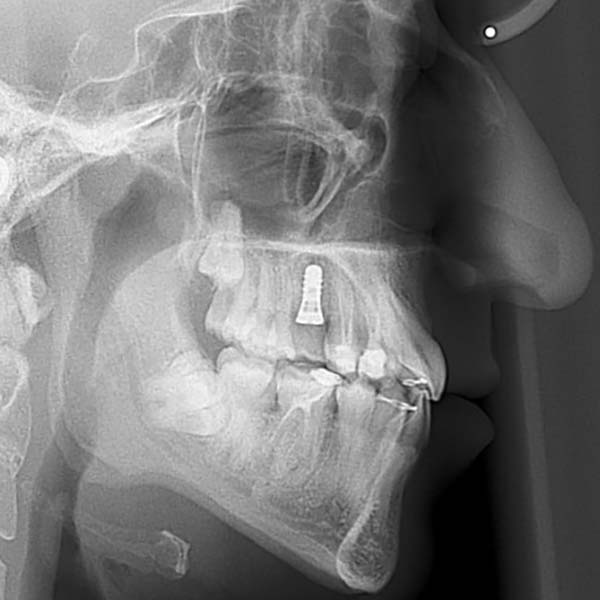

My young friend visited me suffering from a complete Bite collapse, a severe anterior crossbite, in addition to the loss of many of his back teeth. He was so frustrated, thinking that his case is incurable, and this frustration was reflected on his shy smile.

After examining the case, I have conveyed the good news to our friend, that despite the difficulty of his case, we were able to reach a satisfying result through orthodontic treatment. As expected, tooth extraction was nessecary, to open space for the rest of his teeth to arrange and treat the anterior crossbite. At the end of the treatment, most of our friend’s dental problems were treated, and he could smile happily and with confidence.